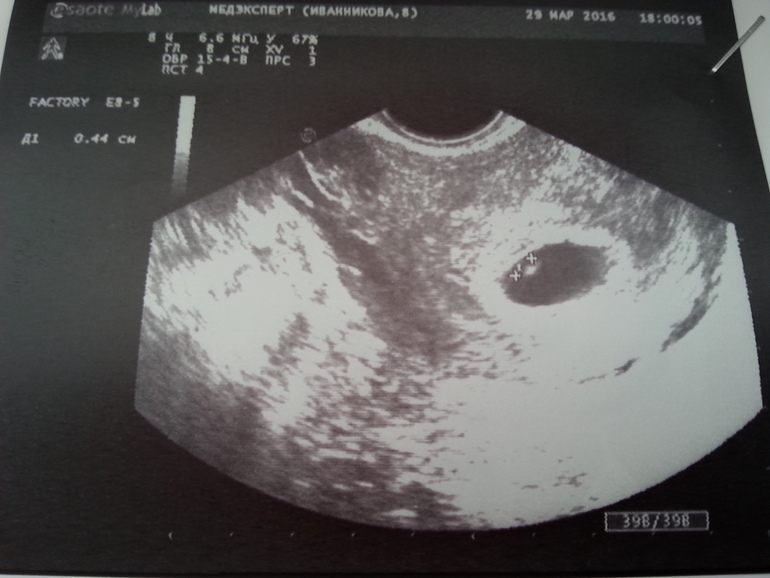

И первое фото нашей бусинки

Тонуса нет, угрозы нет! Развиваемся по сроку! И главное, что сердечко уже бьется!!!

Срок 6 неделек, сегодня 7 пошла)

ПЯ 23 мм

КТР 4,6 мм